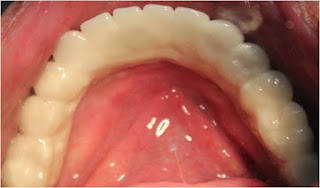

OCCLUSAL VIEW OF ZIRCONIA BRIDGE IN UPPER JAW